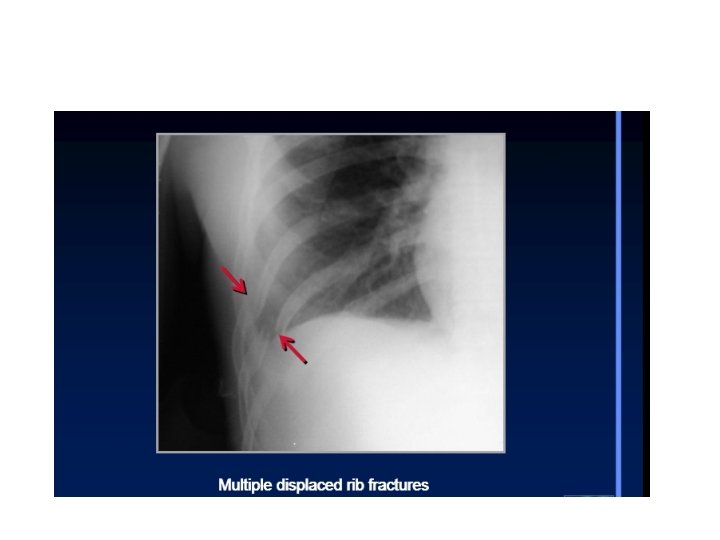

• A broken seg. Of the rib cage which become detached from the

• A broken seg. Of the rib cage which become detached from the rest of the chest wall. . it occur when multiple adjacent ribs are broken in to multiple places. . It is usually accompanied by pulmonary contusion. . causing paradoxical breathing in which the flail seg move in to opposite direction to the rest of the chest wall